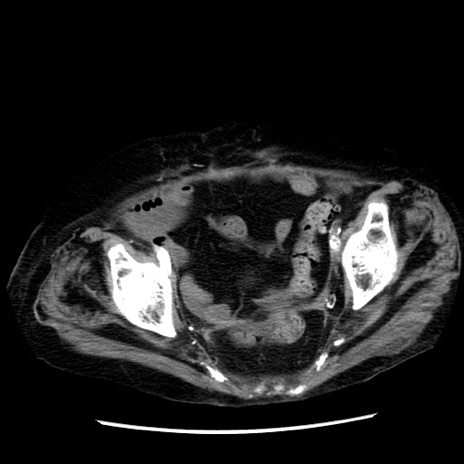

症例14(横断像)

【症例】 90歳代女性

【主訴】 腹痛・嘔吐

【現病歴】今朝から左側腹部痛を認めた。 経過観察していたが、嘔吐を認めたため来院。

【既往歴】 子宮癌術後

【身体所見】 意識清明、BP 127/54mmHg、P 98bpm Sp02 95%(RA)、BT 35.8°C、腹部平坦・軟腸ぜん動音聴取良好、右下腹部圧痛(+) 反跳痛なし

【データ】WBC 9800、CRP 0.46